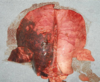

Q

What lesion is shown here?

A

enamel hypoplasia